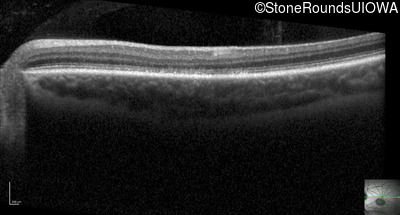

Optical Coherence Tomography - Right - 20/125 sc

Exemplar / OCT Stack

OCT Stack